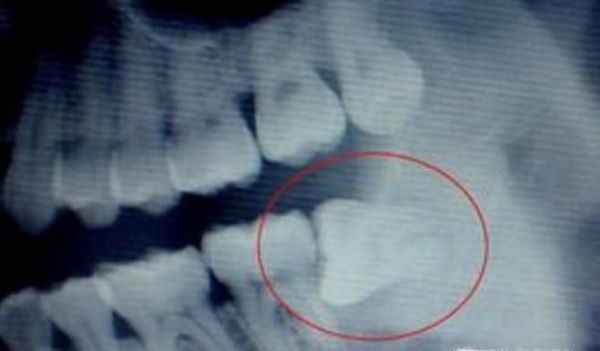

操作方法01、首先,长了智齿的话,如果智齿靠近我们的神经的话,那么这样的智齿是不能拔的,因为如果拔的话,一旦碰到神经的话,那么对我们的身体伤害是巨大的,一般医生也不会建议我们拔的,我们需要定期清理干净我们的智齿处。